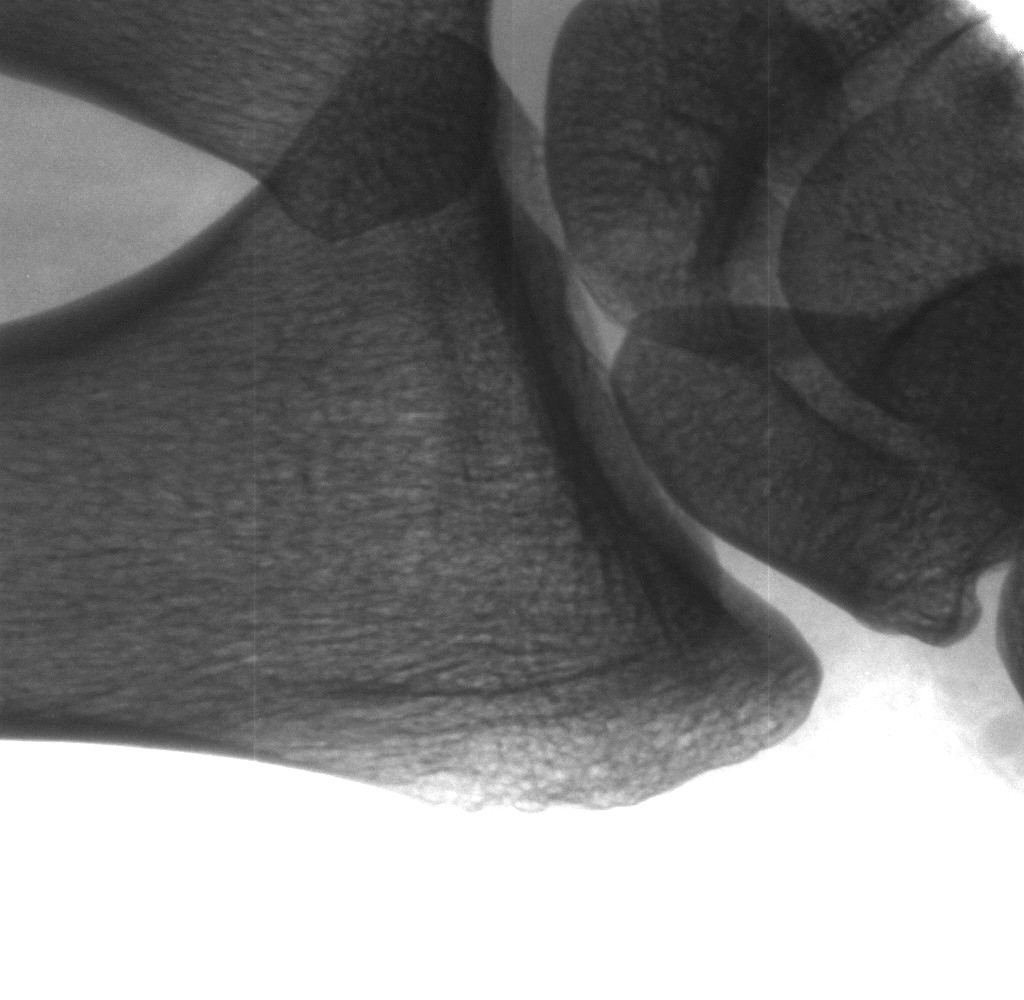

Fingerspitzen (40kV/0.2mA).